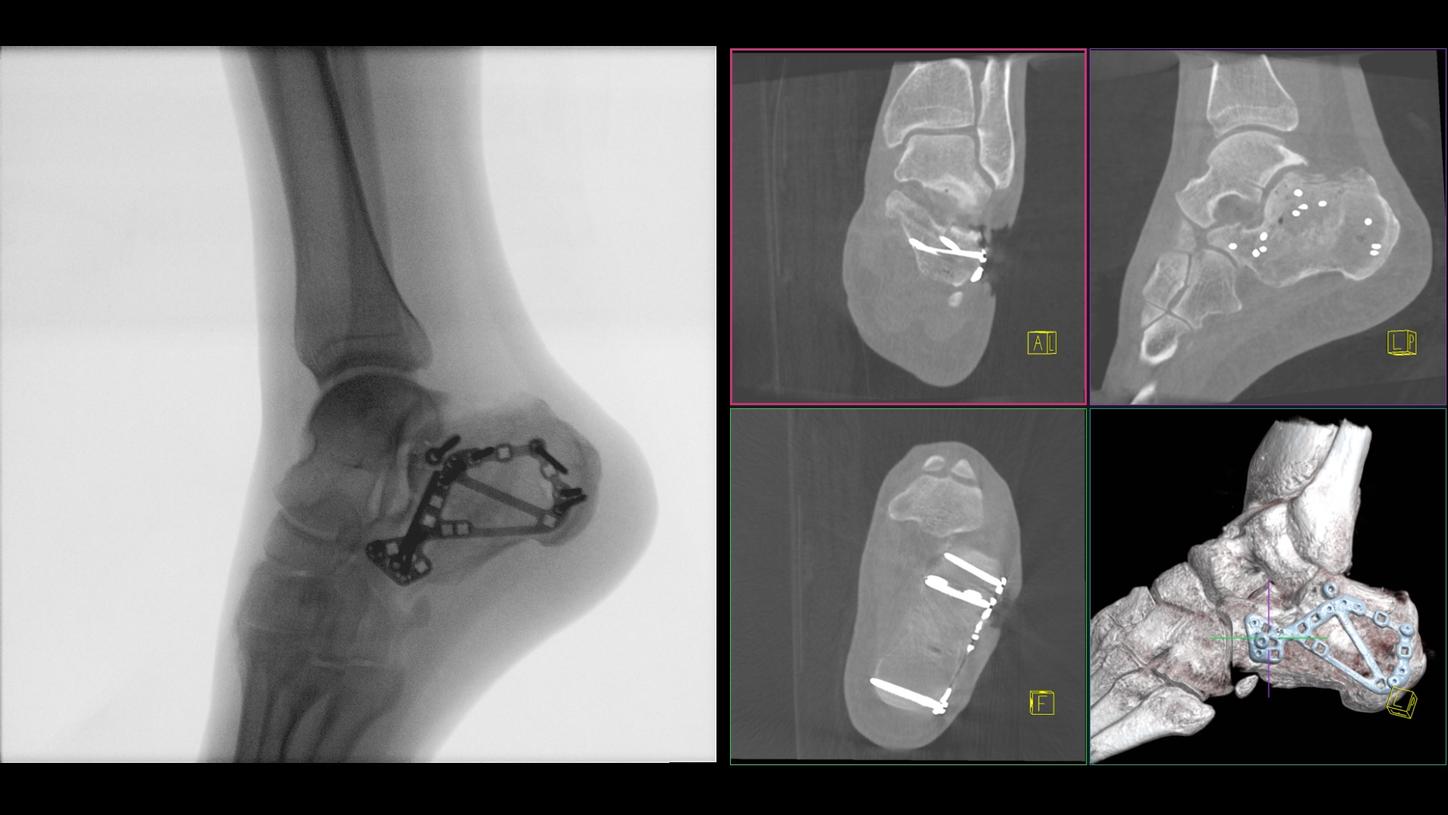

CIARTIC Move already has proven its benefits in a preclinical study1: The system enabled significant time savings for all three anatomical regions included in the study (pelvis, spine, distal radius).

Benefit from precise 2D and 3D visualization of anatomical structures and metallic objects with excellent image quality.